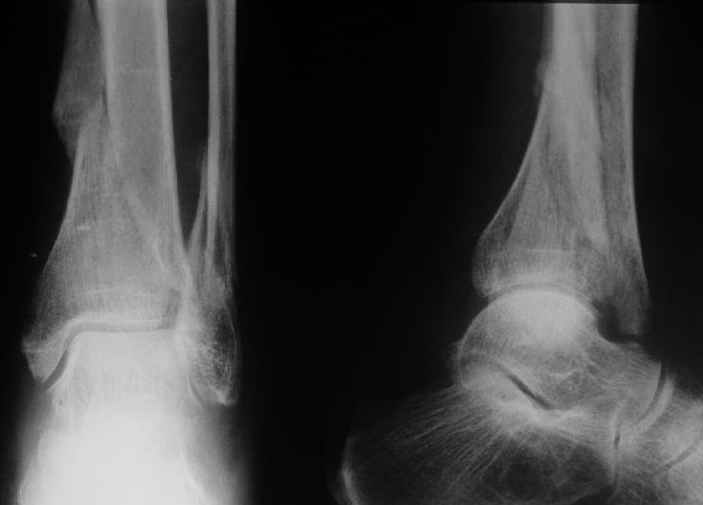

Дама 56 лет 6 недель назад получила спиральные переломы дистальных отделов костей голени. По месту жительства наложили гипс.

Сейчас вот, получается, спохватились. Снимки и КТ в приложении. Какой вариант тут предпочтительнее - открытая мобилизация, репозиция и внутренняя или наружная фиксация? Или ограничиться только резекцией костного шипа над шейкой тарана?Заранее спасибо.A female 56 y.o. 6 weeks ago sustained a fracture of the distal tibia/fibula. At the initial hospital a plaster cast was applied. Now she was referred to our unit. At the moment there is no pain, no obvious mobility. Images and CT attached.What is the best option here? Mobilize the fracture, perform open reduction and internal or external fixation? Or just to cut the anterior spike over the talar neck? THX in advance.

Отправитель: Андрей 30 Август 2004, 00:44

Судя по рентгену, там вполне приличное сращение.Ось сохранена, укорочение - макс. 1,5 см. Чего ещё хотеть? Шип желатепьно убрать. Исключительно, чтобы

Though the upper tibia is not seen on the Xray and thus we cannot exactly see the amount of varus angulation, I presume it must be minimal and acceptable, otherwise you have noted and mentioned the same.